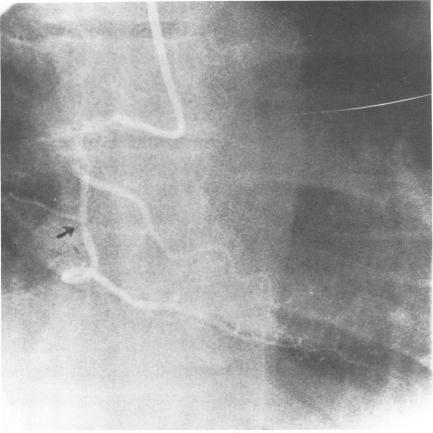

Myocardial infarction is a rare complication of maximal exercise testing.(1) In the case presented here, infarction occurred in a 54-year-old man, 14 minutes after he showed a normal response to maximal multistage treadmill exercise testing. The presence of coronary artery disease had been documented angiographically prior to exercise testing. After infarction, the patient underwent emergency double aortocoronary bypass to the left anterior descending and right coronary arteries with good results. Clinical evidence suggests that the extent of myocardial necrosis was reduced by timely surgical intervention. There is no conclusive explanation for this patient's normal response to maximal exercise testing in the presence of advanced coronary artery occlusive disease followed rapidly by infarction. The value of exercise testing is well established in assessing the existence or severity of coronary artery disease; a normal response, however, cannot be used as an infallible indication that critical coronary artery disease does not exist.

心肌梗死是极量运动试验的一种罕见并发症。(1) 在本文所述病例中,一名54岁男性在对极量多级平板运动试验显示正常反应14分钟后发生了心肌梗死。运动试验前已通过血管造影记录了冠状动脉疾病的存在。心肌梗死后,患者接受了紧急左前降支和右冠状动脉双主动脉冠状动脉搭桥手术,效果良好。临床证据表明,及时的手术干预减少了心肌坏死的范围。对于该患者在存在晚期冠状动脉闭塞性疾病的情况下对极量运动试验的正常反应随后迅速发生心肌梗死,尚无确凿的解释。运动试验在评估冠状动脉疾病的存在或严重程度方面的价值已得到充分确立;然而,正常反应不能用作不存在严重冠状动脉疾病的绝对指标。